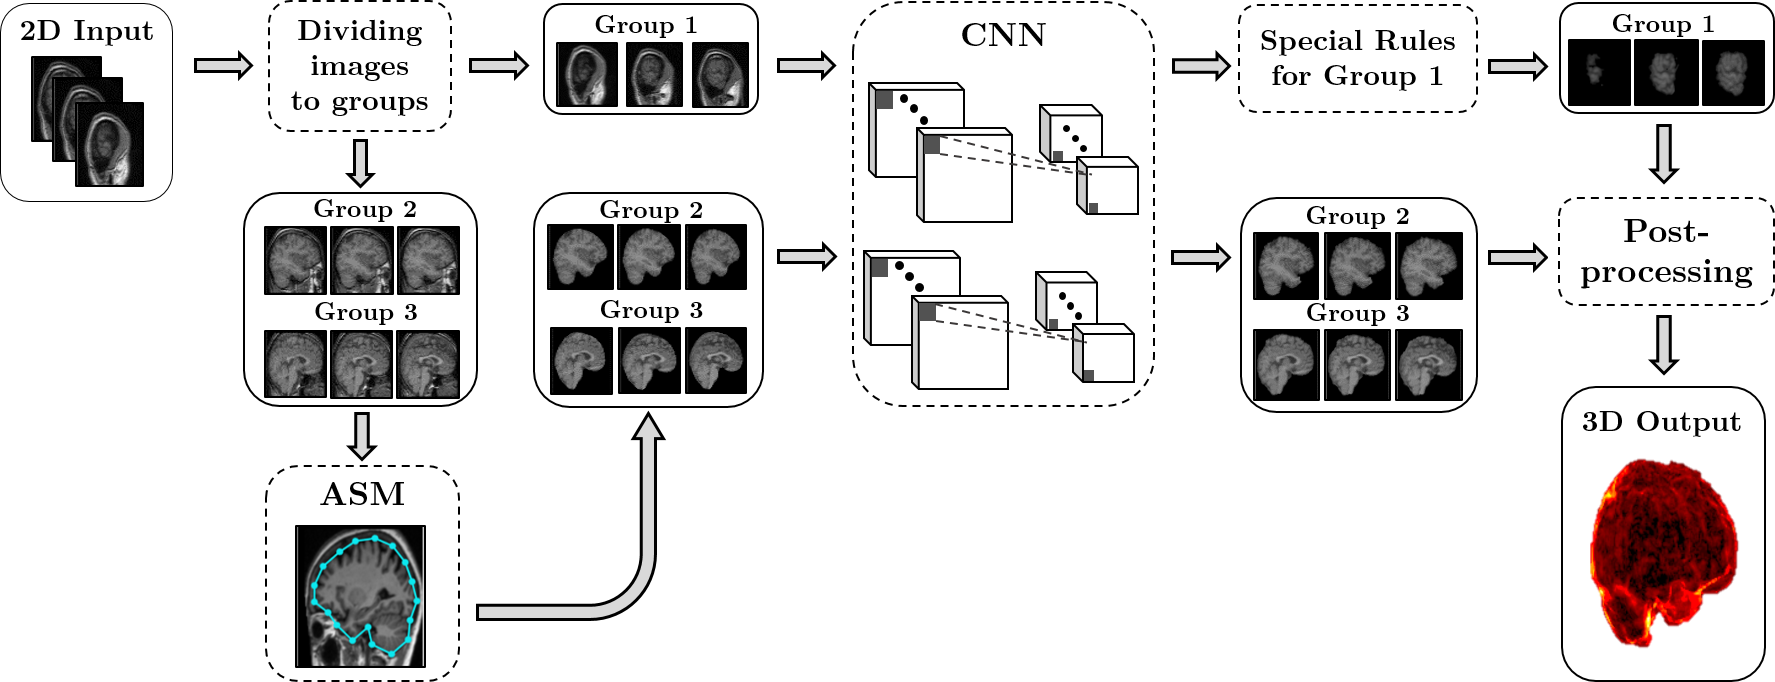

Refer to caption

Figure 1: An overview of our proposed method with 2D input and stacking predicted results to obtain a 3D volume. Firstly, images with similar shape and appearance are divided into three distinct groups, namely Group 1, Group 2, and Group 3. Secondly, to obtain initial masks for all groups, a modified Active Shape Model (ASM) is then applied for Group 2 and Group 3, while a Convolutional Neural Network (CNN) is utilized in Group 1 due to its complex shape with disconnected regions. Thirdly, over-smooth results in Group 2 and 3 are corrected by the CNN (same architecture used in Group 1) for pixels locating near the object’s boundary. With Group 1, prior medical knowledge from brain positions and obtained masks in Group 2, 3 are integrated by special rules to eliminate noisy regions, e.g., skull areas. Finally, all results are post-processed by a conditional random field to alleviate fatal errors by pixel-wise approaches.

In neuroimaging, one can use a three-plane coordinate system to describe a human body’s standard anatomical position. These imaging planes are the transverse plane, the sagittal plane, and the coronal plane. In ASMCNN, we choose to process 2D slices in the sagittal plane as human brains are nearly symmetrical concerning the mid-sagittal plane. It allows us to predict the general shapes of brain regions with better accuracy. ASMCNN comprises of three main stages: (1) dividing images into groups, (2) applying ASM to detect initial brain boundaries for images in specific groups, and (3) constructing CNN for precise segmentation, along with performing different post-processing methods for different groups to refine segmentation contours. The flowchart of our system is given in Figures 1. Three main stages of the proposed method are presented in the following subsections.